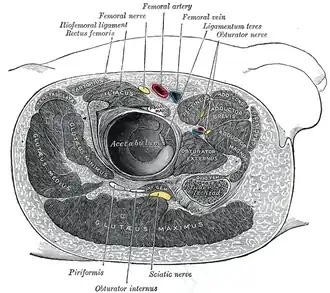

Structures surrounding right hip-joint (gluteus maximus visible at bottom)

Structures surrounding right hip-joint (gluteus maximus visible at bottom) -